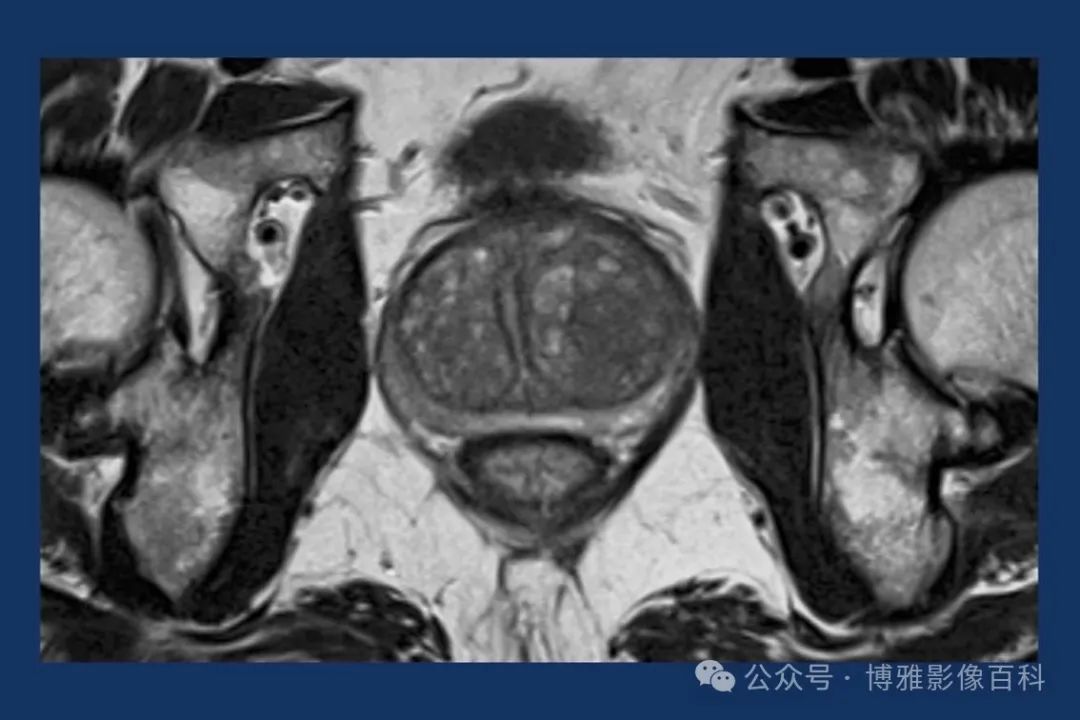

MR 解剖学

前列腺良性增生患者的轴向T2 图像,其他方面正常。外周带是一薄层均匀的高信号,边界清晰连续性的低信号包膜。移行带通常表现为不均匀中等信号,病灶被边界清楚的BPH良性前列腺增生结节所取代。精囊具有均匀T2高信号。未见淋巴结肿大。